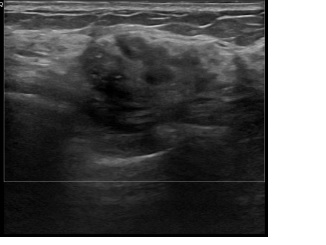

상기환자는 외부검사이상소견으로 내원하신 60대초반

여성분으로 의심스러운 우측혹 조직검사 시행해 침윤성암으로 진단되었습니다